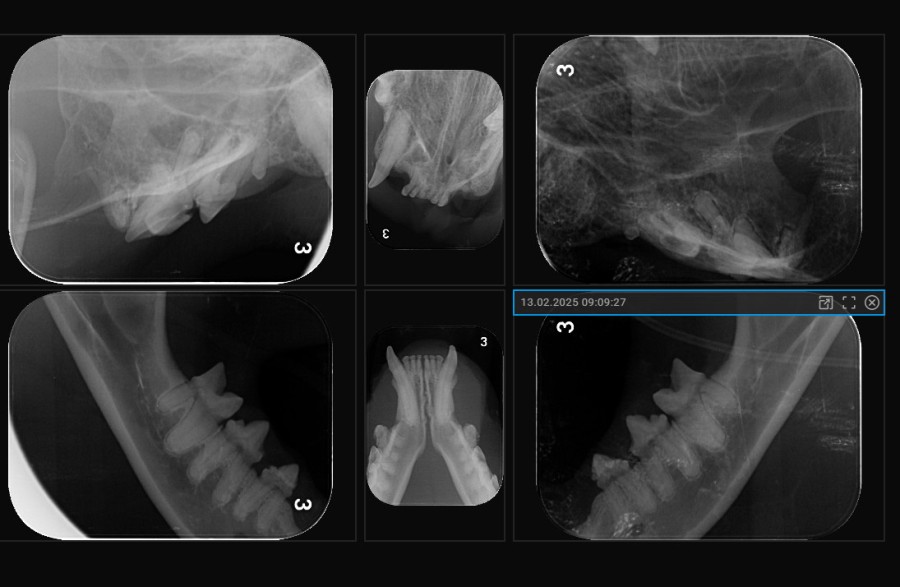

Dentales Röntgen

Eine Zahnsanierung ohne die Möglichkeit des Zahnröntgen zu haben und dieses auch zu nutzen, ist heutzutage medizinisch falsch. Grade bei Katzen gibt es häufig stark schmerzhafte Erkrankungen der Zahnwurzeln, die Sie nur mit in Narkose angefertigten Röntgenbildern erkennen und entsprechend behandeln können. Bei diesen sogenannten Resorptiven Läsionen (früher FORL), lösen sich in einem stark schmerzhaften Prozess die Wurzeln einiger oder gar aller Zähne auf, welche dann gezogen werden müssen.